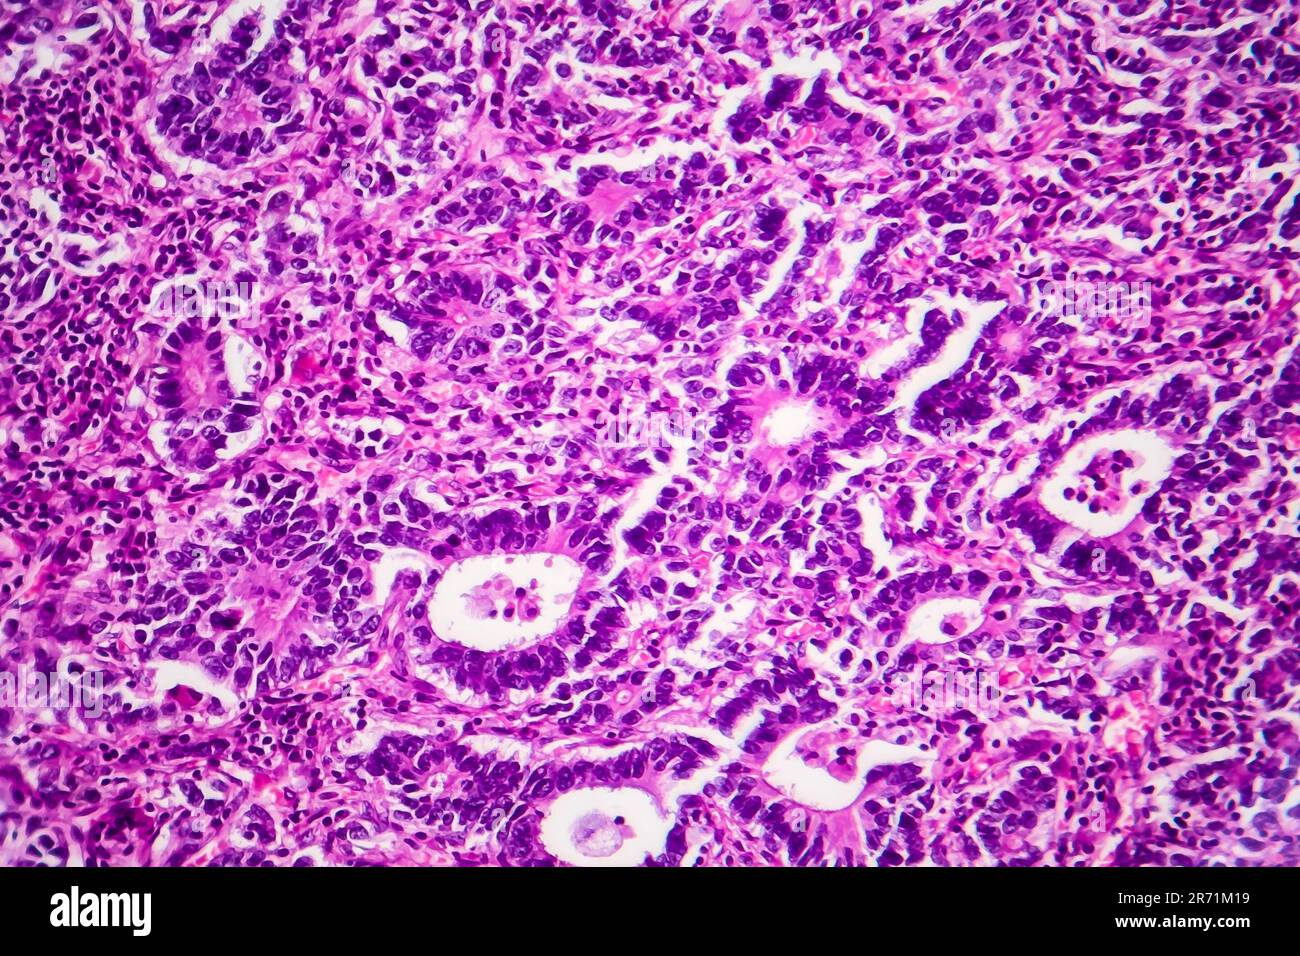

Adenokarzinom des Magens, Lichtmikroskop, Foto unter dem Mikroskop